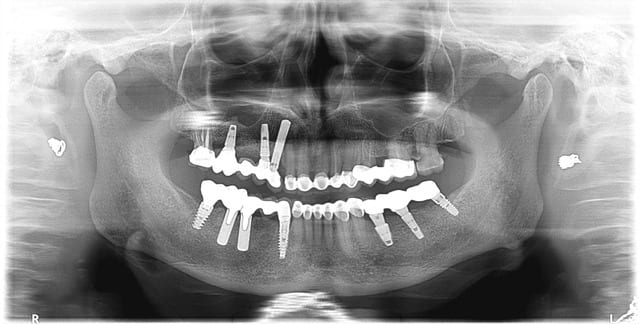

la patiente a des implants artisanaux posés une vingtaine d'années plus tôt... mais qui tiennent bon

dans un 1er temps (fevrier 09) extraction de 15 greffe et pose de 2 implants en position de 14 et 16 (soulevé crestal)

mi juin 09 contrôle et pose du bridge sur implants

mi mars 2010 (+ 9 mois) contrôle pas ou très peu de perte osseuse

Pour le cas de sinclair qui est tres interressant tu nous montres les radios de tes 2 implants 14 16 qui me semble etre des astra qui sont bien posé avec un choix de vis sans pb mais tu ne nous montres pas le même raisonnement avec les autres implants notamment l implant en 44 ou 45 (je suis désolé je n ai plus la radio en face de moi)qui semble présenter un elargissement au niveau du col implantaire. aurais tu une explication? alors que les implants ancestraux sont semble t il stable meme si comme le montre ta premiere pano les vis de transfixation se sont cassées. en revanche excellente idée de faire un inlay core en lieu et place des piliers implantaires.